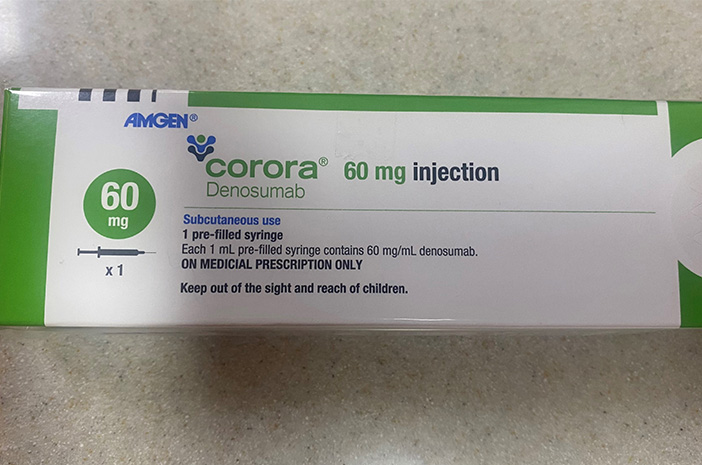

Denosumab yang di Indonesia tersedia dengan nama dagang Corora, merupakan inovasi penting dalam pengobatan osteoporosis.

Corora hadir dalam bentuk larutan injeksi yang mengandung Denosumab 60 mg per prefilled syringe.

Dosis yang direkomendasikan adalah satu suntikan (60 mg) setiap enam bulan sekali, diberikan secara subkutan atau di bawah kulit. Penyuntikan dapat dilakukan pada bagian perut, paha atas, atau lengan bagian luar, sesuai anjuran tenaga medis.

Corora harus digunakan dengan resep dokter.

No registrasi BPOM: DKI2441501343A1